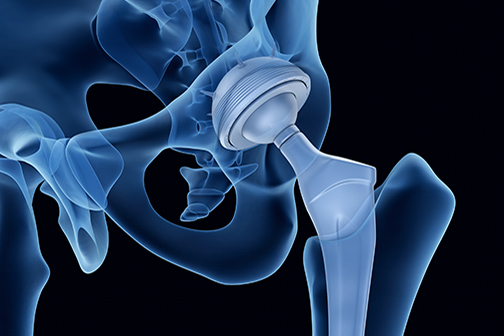

LSU Health New Orleans Pain Protocol Eliminates Need for Opioids Following Knee Replacement in Most Patients

A study led by Vinod Dasa, MD, Professor of Orthopaedics at LSU Health New Orleans School of Medicine, reports that a novel surgical pain management strategy following total knee arthroplasty (TKA), or total knee replacement, provided pain relief without opioids. The researchers also found that changing prescriptions for opioids at discharge from automatic to upon request dramatically decreased opioid use. More

LSU Health New Orleans Study Reports Majority of Patients Recover from Knee Replacement Without Opioids

A retrospective case series study led by Dr. Vinod Dasa, Professor of Clinical Orthopaedics at LSU Health New Orleans School of Medicine, reports that more than two-thirds of the patients who underwent total knee replacement did not need opioids for postoperative pain. Results are published in the Journal of Orthopaedic Experience & Innovation. More